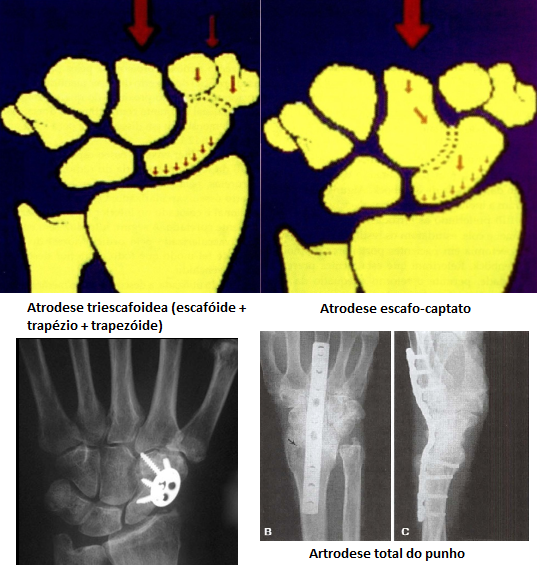

• Dentro do tratamento cirúrgico visando salvação, quais as principais artrodeses podem ser realizadas (3)?

A

• Atrodese escafo-captato

• Diminui mobilidade

• Carga → passa pela fossa do escafóide

• Preensão dos dedos funcional

• Atrodese triescafoidea (escafóide + trapézio + trapezóide)

• Artrodese total do punho (cirurgia final)

• Perda da mobilidade do punho